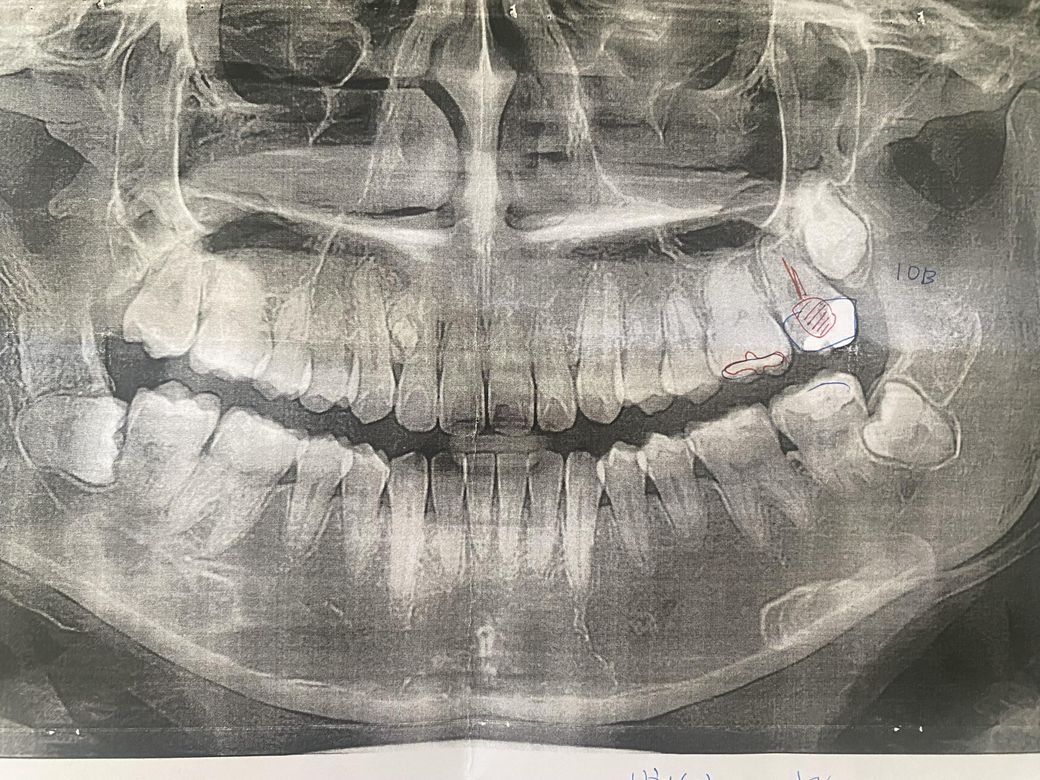

저 아래턱에 있는 치아 빼야하는 사랑니인가요?

7월 초에 엑스레이 찍은겁니다.

아래턱에 사랑니들이 있는데요,

지금 당장 빨리 빼야하는 사랑니들인가요?

위에 사랑니는 굳이 안빼도 되는거죠?

왼쪽사랑니는 난이도가 많이 높은가요...

아래턱에 있는 치아 사랑니는 꼭 뺄 필요는 없어보이지만 정기 검진하면서 문제가 생기면 발치하시면 됩니다.

하악에 있는 사랑니는 완전히 매복되어 있기 때문에 발치를 필요로 하지 않습니다. 하지만 치아 주변에 문제를 발생시킬 위험이 있다면 발치를 하는것이 좋습니다. 주기적으로 치과에서 검진을 받으며 발치 여부를 확인하는 것이 좋습니다.

현재 사랑니가 매복되어 누워있는 것으로 보이며 ,이경우 발치가 필요로 됩니다. 방치시에는 앞의 어금니에도 손상을 줄수 있습니다. 발치후에 1-2주간은 붓기 및 통증이 나타날수 있으며, 만약 통증과 붓기가 많이 심한 것이 아닌 경우에는 크게 문제가 되지는 않기에 지켜보셔도 괜찮습니다.

아래쪽 사랑니는 별다른 이유가 없다면 발치를 하지 않아도 크게 문제가되거나 하진 않을것같습니다.